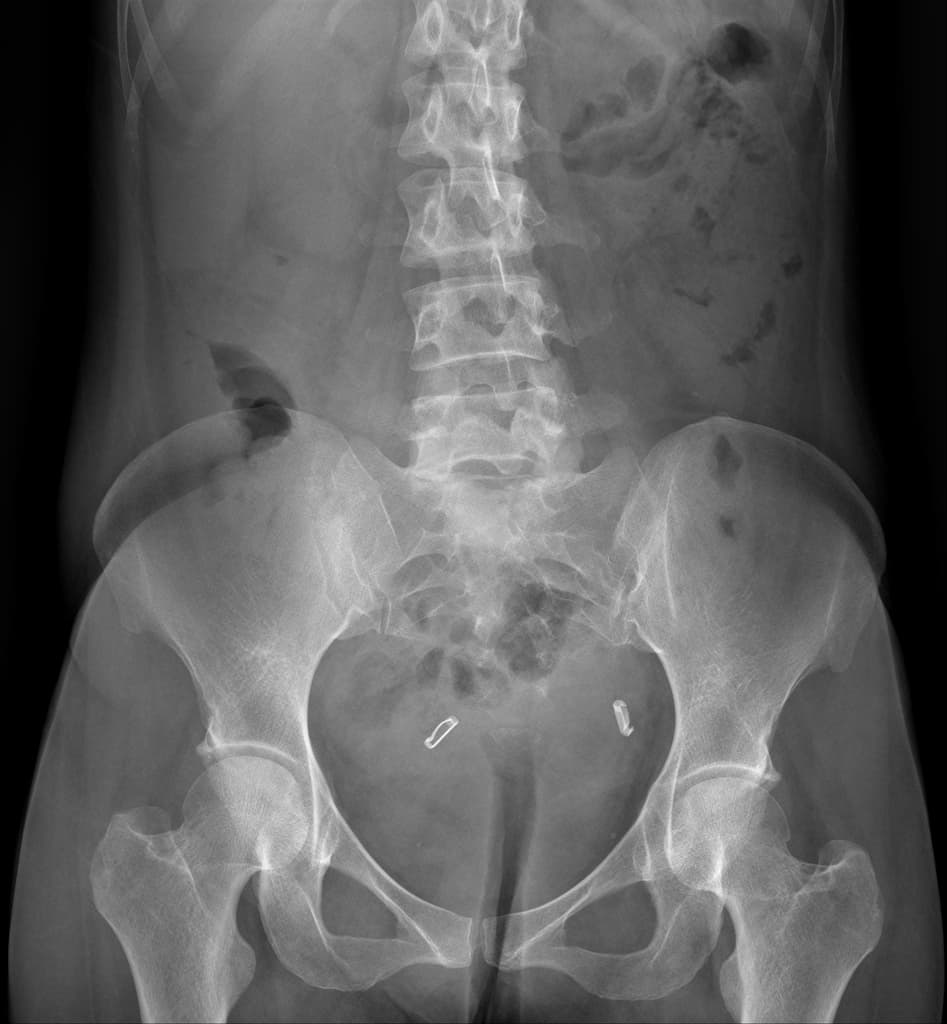

MRCP (Chụp cộng hưởng từ đường mật tụy) Có một hình khuyết tín hiệu dạng tròn kích thước 4,5 mm ở đoạn cuối ống mật chủ, ngang mức nhú tá, gợi ý sỏi trong ống mật. Ống mật chủ giãn (8,0 mm) và có một ít mật đặc bên trong. Giãn nhẹ đường mật trong gan. Không thấy sỏi khác trong đường mật.

- Sỏi đoạn cuối ống mật chủ kích thước 4,5 mm và giãn nhẹ cây đường mật.